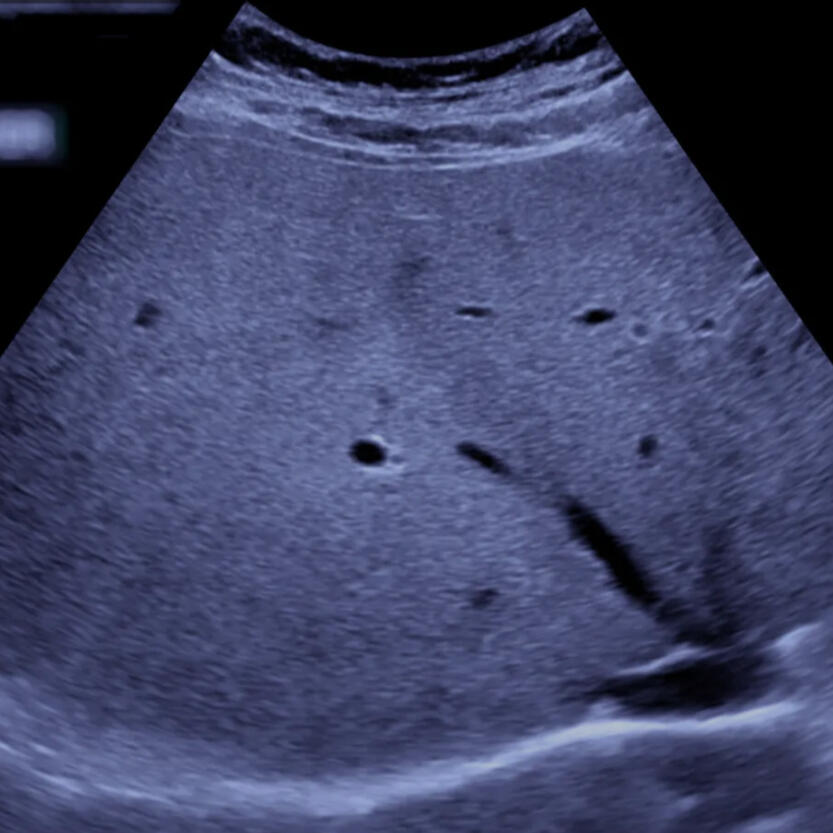

- Profesionalūs echoskopiniai tyrimai (krūtinės ir pilvo organai)